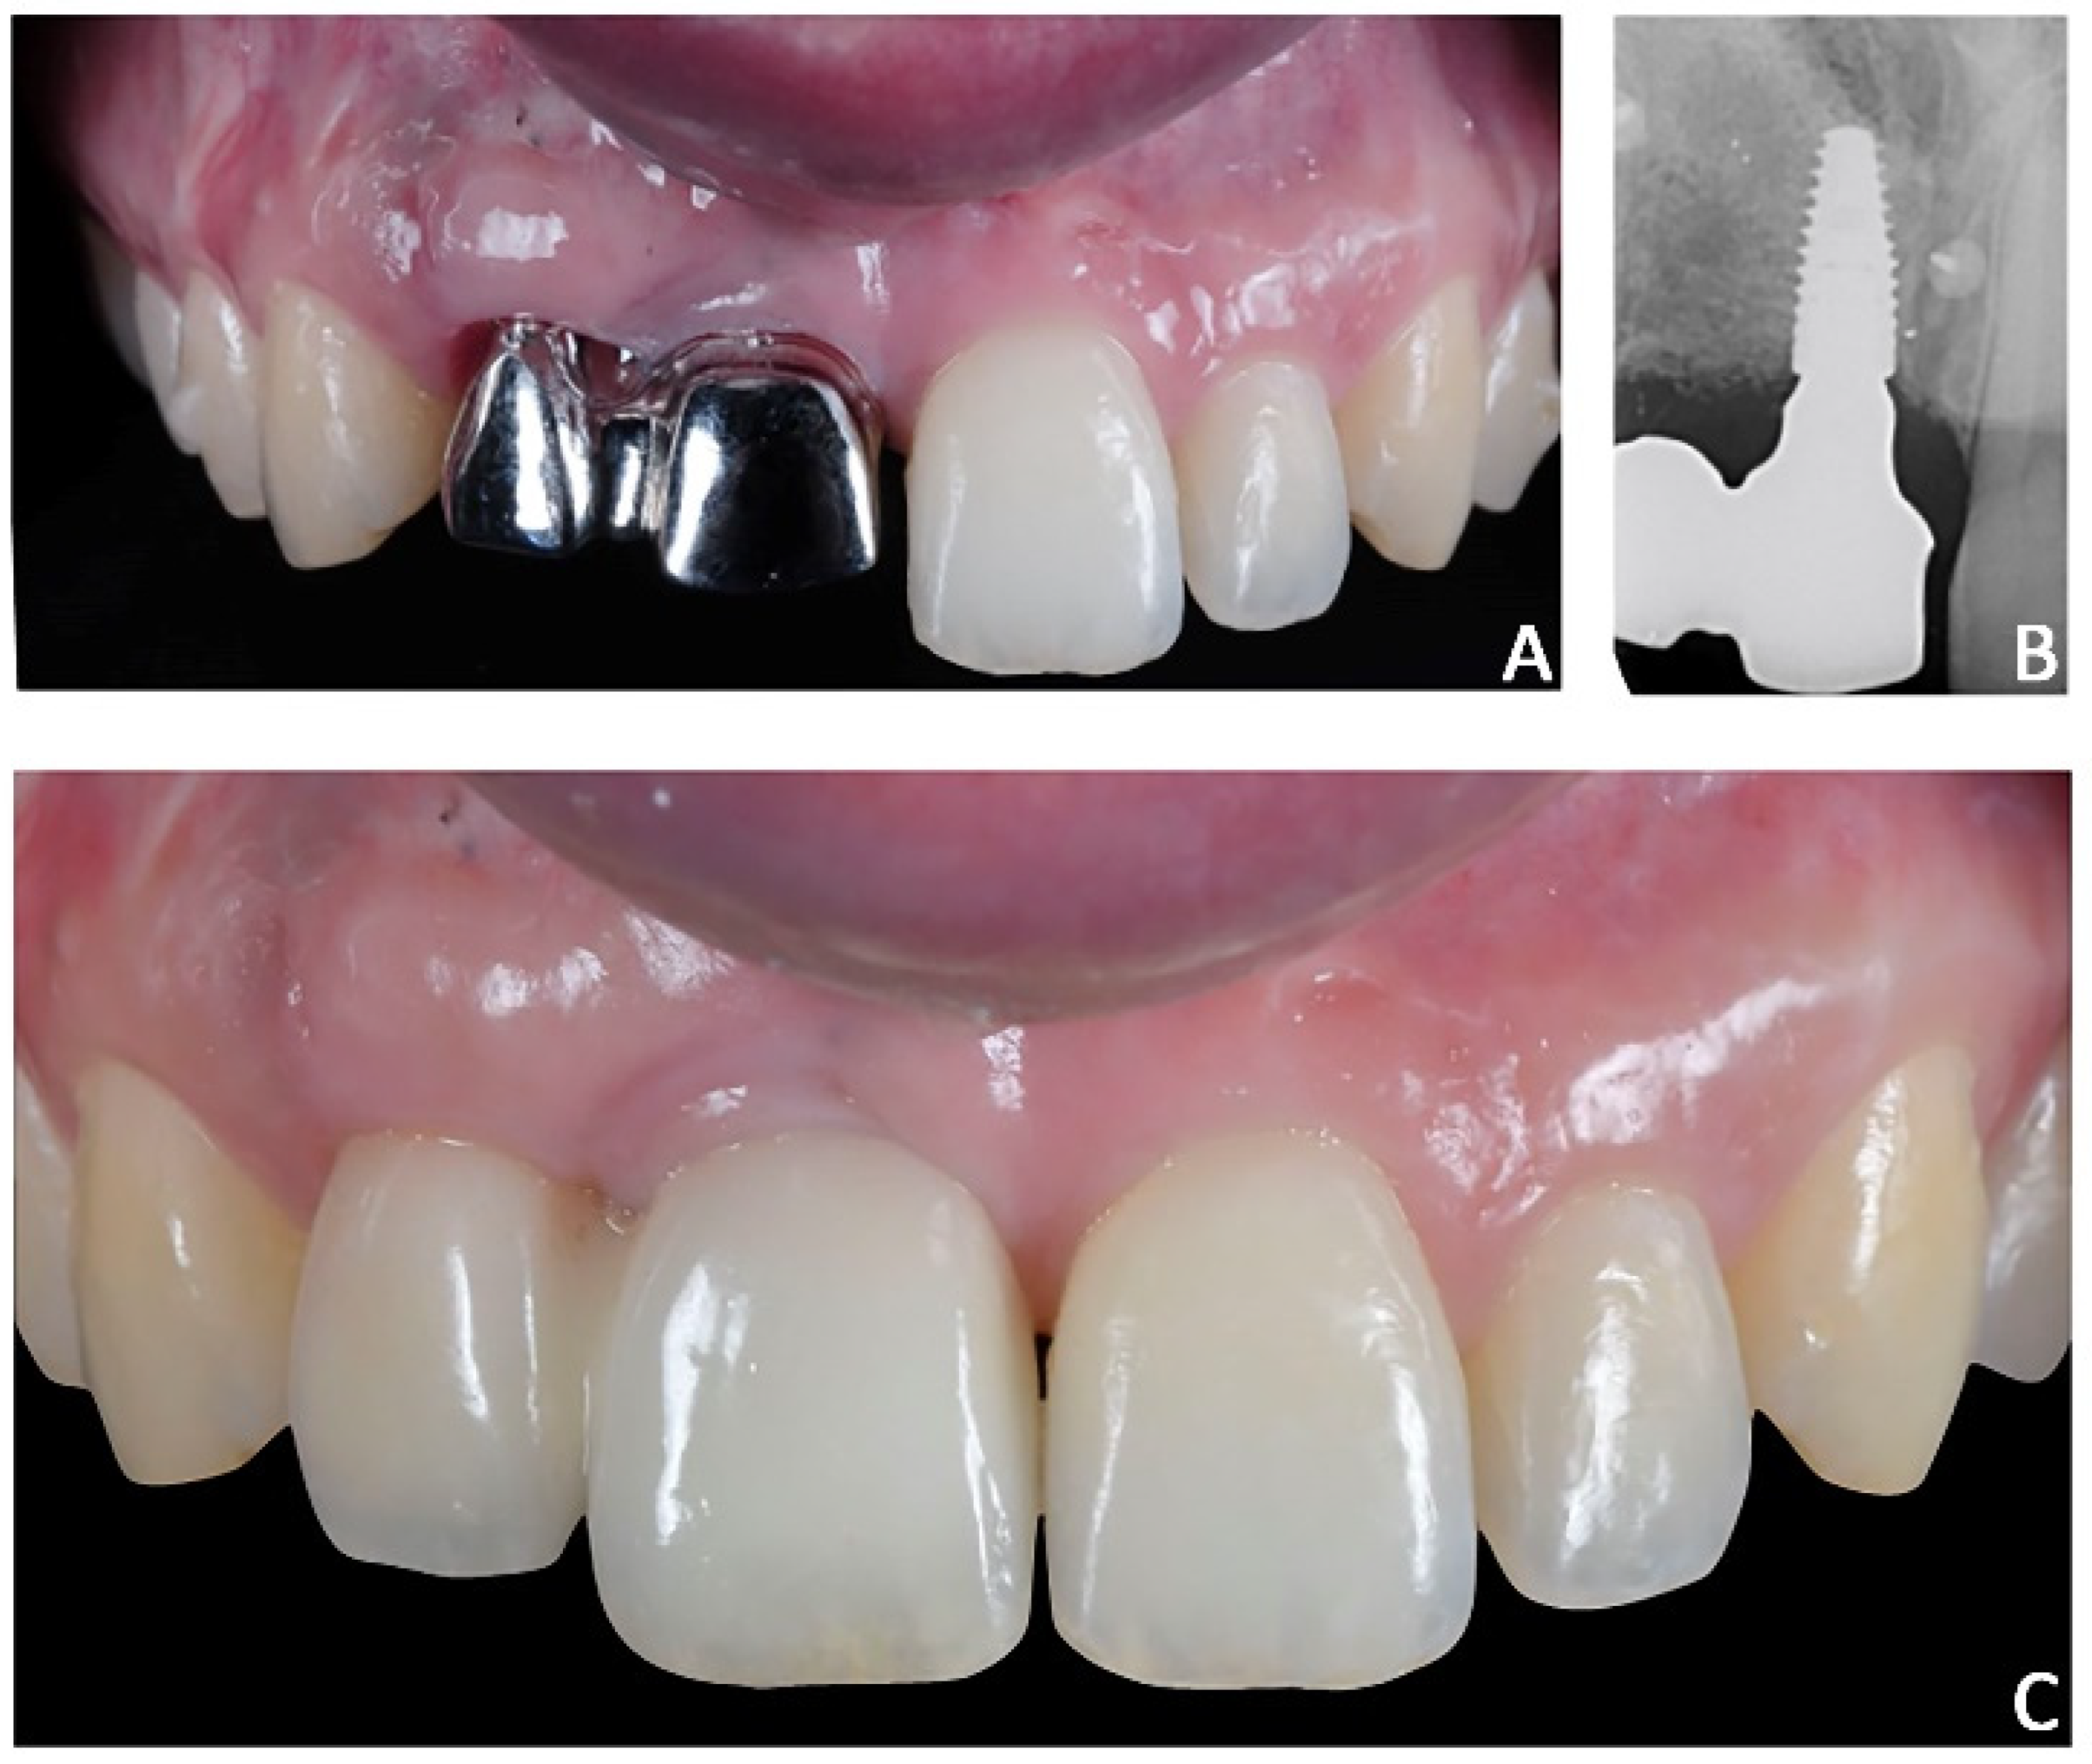

Figure 14. Case 2. Final prosthesis using milled cobalt-chrome structure and feldspathic porcelain. (A) Milled cobalt-chrome structure; (B) radiographic evaluation; (C) prosthesis veneered with feldspathic porcelain.

Final prosthetic rehabilitation. After orthodontic treatment, two intra-oral scans were registered: (1) an intra-oral scan with the position of the implant and surrounding soft tissues and (2) an intra-oral scan with the provisional prosthesis. The two files were sent to the laboratory and would replicate the relationships between the soft tissues and the temporary prosthesis in the final prosthesis. After prototyping the 3D model of the maxillary arch, the lab technician projected a milled cobalt-chrome structure that was veneered with feldspathic porcelain (Figure 14).